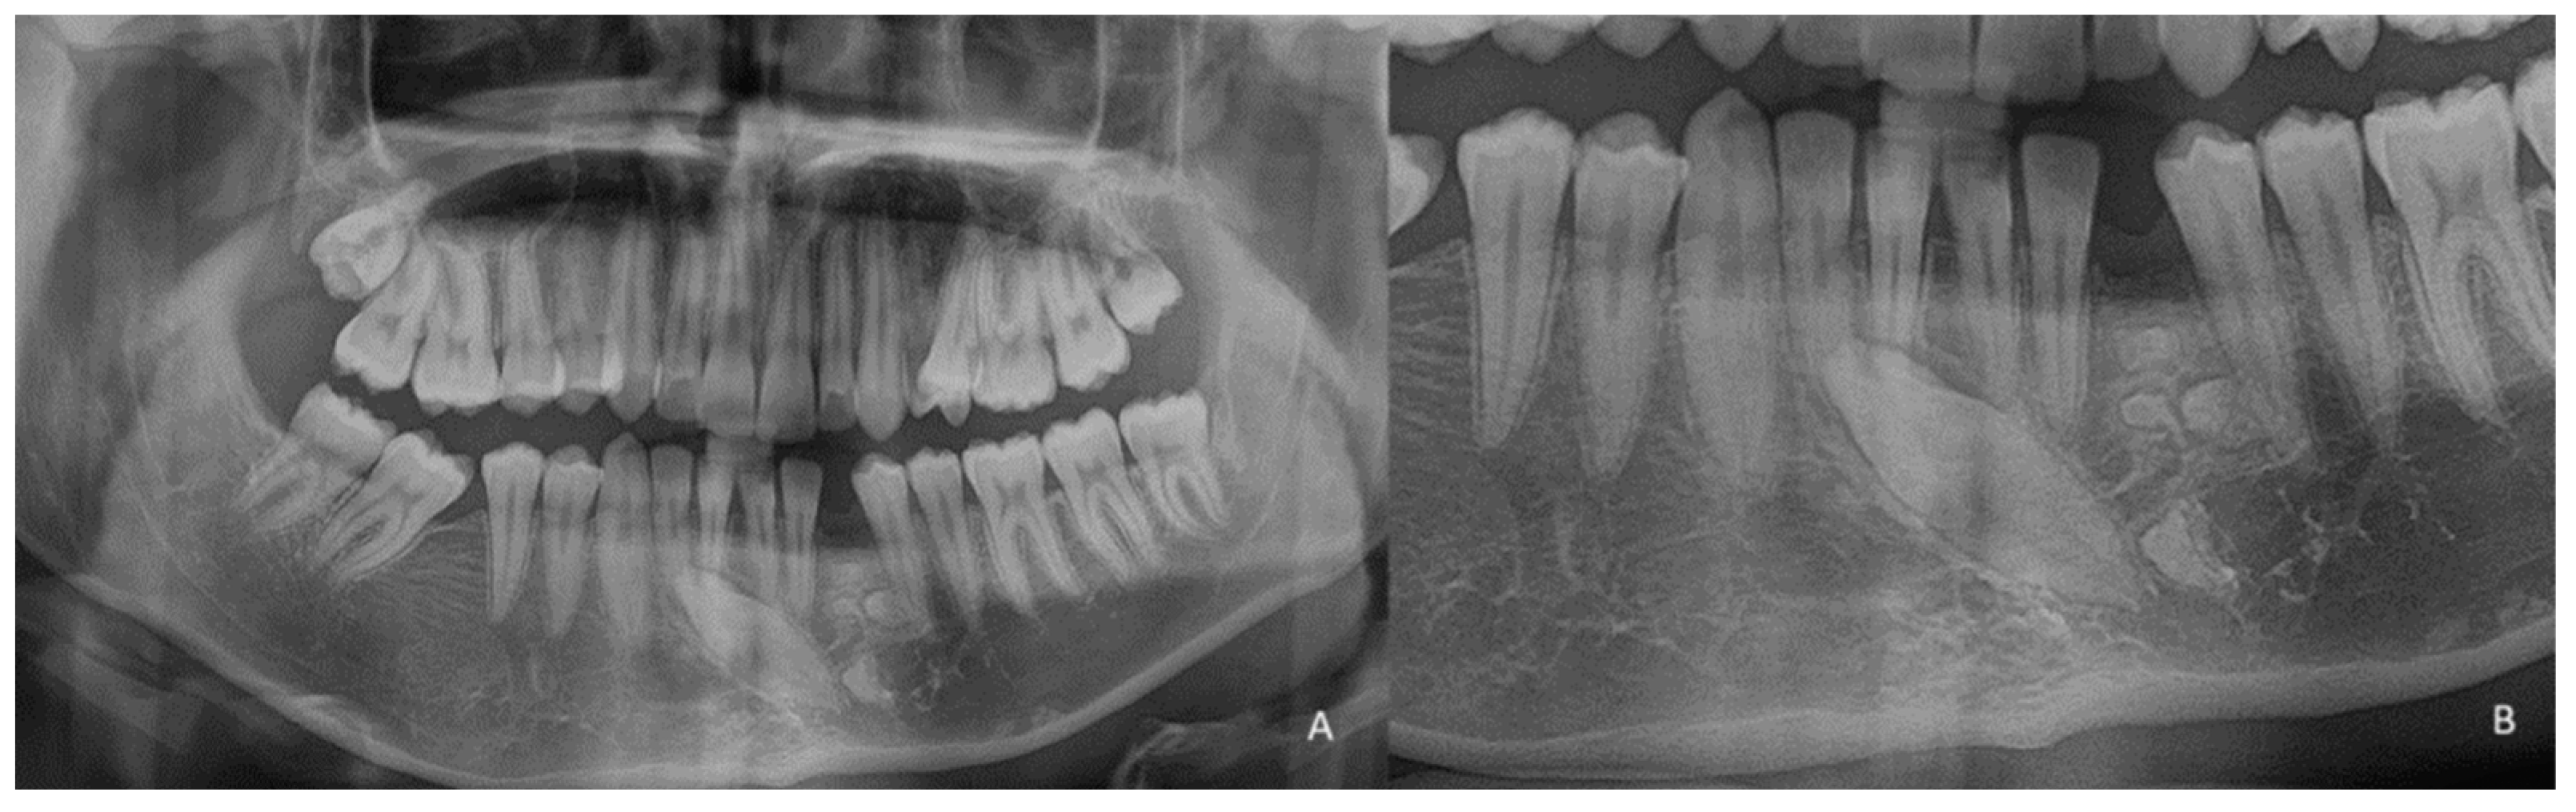

1.2. Case Number 2